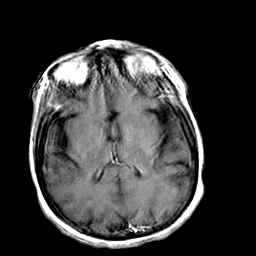

Creutzfeld-Jakob disease: gadolinium enchanced T1-Weighted MR -- Slice #13

[Home][Help][Clinical] Slice 13